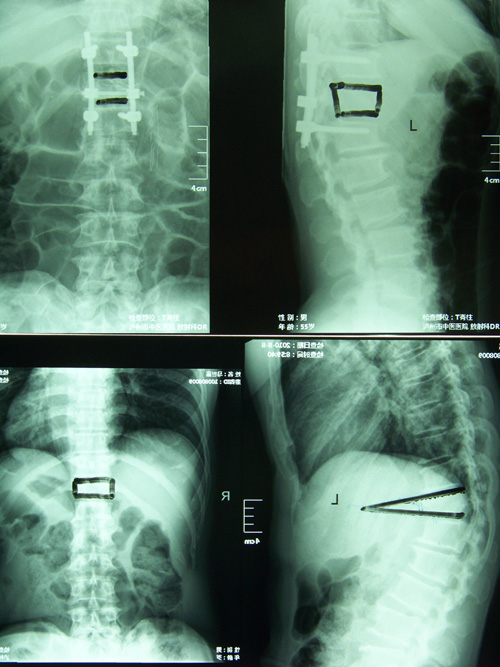

• ????????????????????????????????? 骨傷一科成功開(kāi)展經(jīng)皮穿刺椎體成形術(shù)???????????????????????????????????????????????? 骨傷一科 肖言潔??? 骨傷一科近日成功開(kāi)展了高齡患者胸腰椎壓縮性骨折經(jīng)皮穿刺椎體成形術(shù),該手術(shù)方式...